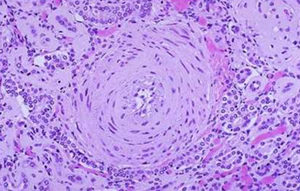

Aschoff Bodies

pathognomonic heart lesions in RF

Rheumatic Myocarditis

Aschoff bodies are seen between myocardial bundles as paravascular fusiform collection of mononuclear cells around fibrinoid necrosis